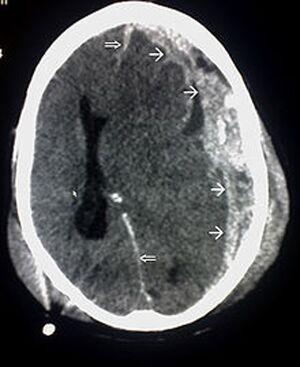

Die weißen Pfeile kennzeichnen die Blutergüsse im Gehirn - Glitzi queen00 commons.wikimedia.org, CC0 1.0

Die Gehirnerschütterung stellt eine Prellung des Gehirns dar. Schwere Kopfverletzungen sind beim Sport glücklicherweise eher selten. Jedoch sind Gehirnerschütterungen zB beim Fußball als Folge von Zusammenstößen mit Spielern beim Kopfball oder dem Torpfosten leider öfter zu sehen. Die Verletzten klagen über teilweise heftige Kopfschmerzen, Schwindelgefühle, manchmal auch über Übelkeit und Erbrechen, zudem können kurze Bewusstlosigkeit und Erinnerungslücken auftreten.